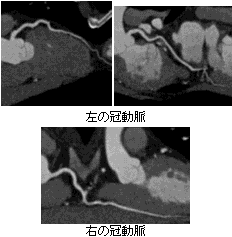

写真 CPR画像

CPR画像:血管の太さや狭窄の程度、石灰化、 血栓の性状など詳細な画像が得られます。